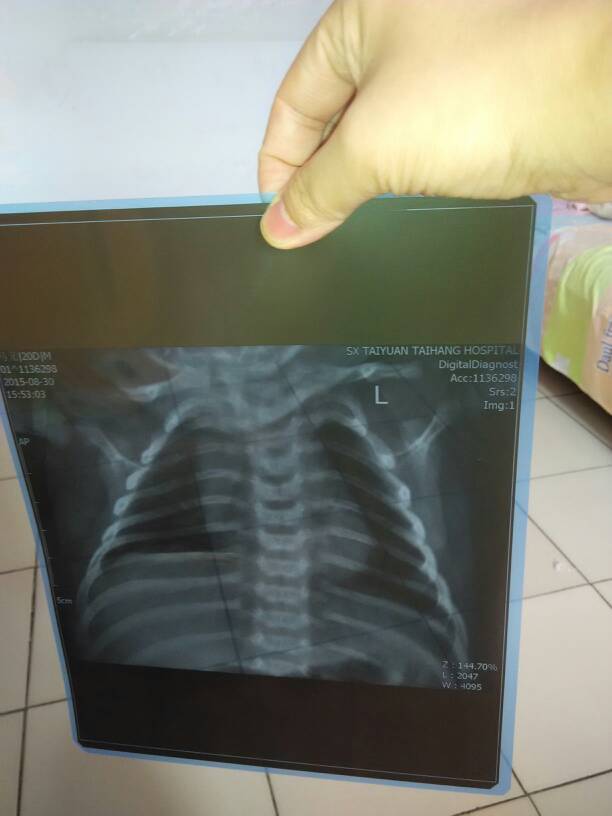

昨天去洗澡,发现有鼻塞!拍了胸片,诊断为新生儿肺炎! 点击展开 匿名用户 2015-08-31 12:20 满意回答 目前胸片是明确支持肺炎诊断的,肺炎建议是输液铜怠清治疗的,而且新生趋抓儿大多都是要住院的,也有门诊治疗的。当然如果宝宝只是鼻阻,没有其他任何表现。精神胃口都好司药,一般1周左右就会好的 cn#GfpkVaQau 2015-08-31 12:28 宝宝知道提示您:回答为网友贡献,仅供参考。 相关问题 我儿子刚生第5天,医生听诊说是新生儿肺炎,叫住院治疗,然后我去拍了一个胸片,结果是,检查所见: 新生儿,有点鼻塞,睡觉嘴巴有点吐泡泡,爱睡觉,肯吃奶,但医生说她可能有新生儿肺炎,要转保温箱,但问 儿子今天出生三天了,出生时医生说是脐带绕颈一圈造成孩子缺氧,胎心也不好,在监护室呢,今天做个磁共振和胸片,胸片诊断新生儿肺炎,磁共振说缺氧性脑病,跪求医生解答!